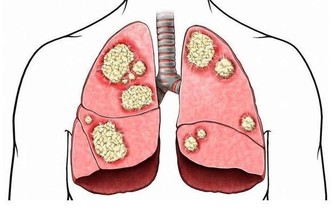

缺鐵性貧血是小細胞低色素性的貧血,放在顯微鏡下看我們血液中的紅細胞,顏色很淡,形狀也比正常情況下小很多。缺鐵性貧血的發病率非常高,在我國,差不多每5位女性中就有1個是缺鐵貧的患者。

缺鐵性貧血不僅僅是貧血這樣簡單,它能夠導致機體免疫力的下降,降低人們對疾病的抵抗能力。而且,缺血即缺氧,骨骼肌中的呼吸酶、線粒體氧化酶等含量都會下降,致使患者出現乏力、氣喘、活動力下降等表現。

缺鐵貧的患者需要尤為小心心血管事件,貧血是個全身性的疾病,機體處於一個缺氧的狀態,所以全身的各個臟器都會受到影響,只不過,相較於其他的器官,心臟、大腦這些用氧量更多的器官,受到的波及會更大,既往有冠心病、腦梗等患者需要格外小心。